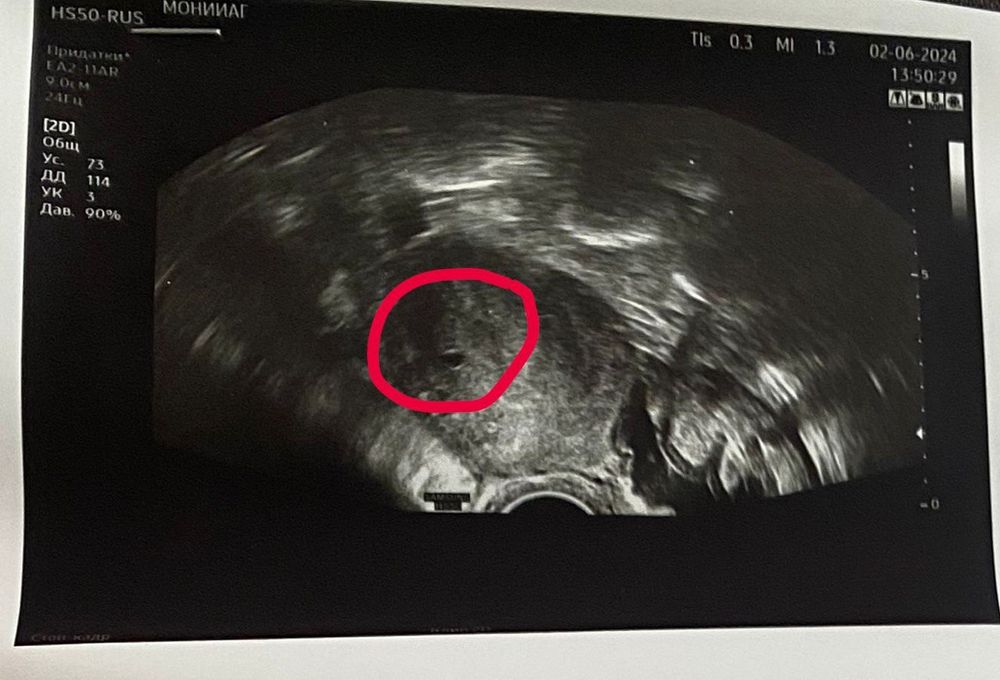

Ирина, пока чудеса продолжаются 😊 У меня разрыв кисты в правом яичнике. Редуцировали (удалили) часть яичника, но сохранили 🙏 Внематочную не нашли. Ре на узи сегодня видела что-то вроде маленького плодного яйца, которое соответствует хгч 800, но у меня было 3488. Остается понять: беременность развивающаяся или неразвивающаяся

Maria, хотели удалять полностью трубу, но не стали. Все трубы и яичники на месте) У меня разрыв кисты в правом яичнике. Редуцировали (удалили) часть яичника, но сохранили 🙏 Внематочную не нашли. Ре на узи сегодня видела что-то вроде маленького плодного яйца, которое соответствует хгч 800, но у меня было 3488. Остается понять: беременность развивающаяся или неразвивающаяся